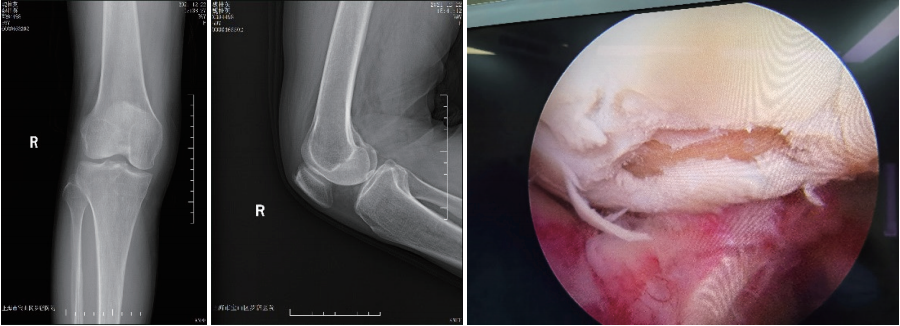

从退休开始,王阿姨一直是小区广场舞队领队,每天带着大家积极锻炼身体。然而年过60岁,王阿姨开始觉得膝盖隐隐地痛,开始没当回事,只当是年纪大了腿脚不好。但不到一年,疼痛越来越厉害,以至于稍微站立一会都会异常疼痛难忍,只得暂时忍痛放弃了跳舞。无奈到了医院,医生听完病史,详细做了体格检查,拍了X线片后诊断:右膝骨性关节炎(Osteoarthritis, OA)。由于膝关节慢慢开始出现畸形,软骨有了明显的磨损,合并有半月板损伤,王阿姨接受了一次关节镜手术,术中可以看到明显缺损的软骨。医生给出了治疗建议,如果痛得厉害就需要做关节置换来治疗,如果疼痛还能忍受可以先打打封闭吃吃药,将来再置换。

王阿姨右膝关节X线检查和关节镜检查。X线检查诊断右膝骨性关节炎,关节镜下可见内侧股骨髁有大片软骨缺损